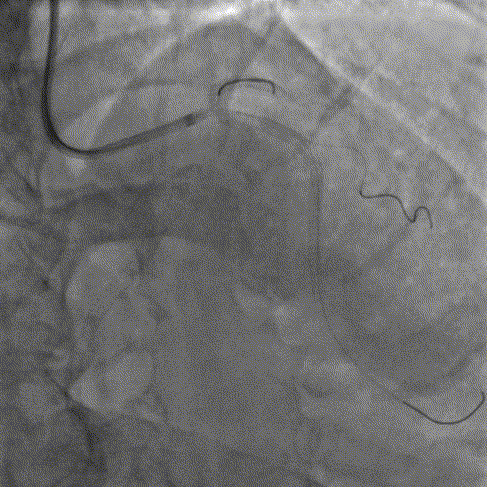

球囊预扩

选择不同尺寸的预扩球囊逐级预扩张病变,复查造影狭窄减轻不明显。为了解血管真实情况,遂启用IVUS检查。

术前腔内影像学IVUS指导

IVUS提示血管内钙化严重,最小管腔面积不足 4mm²;遂考虑启动IVL治疗。

冲击波球囊治疗

2.5*12mm@4atm 冠脉血管内冲击波导管反复进行8个周期治疗,经IVUS检查提示最小管腔面积增加至4.88mm²;随后选取后扩张球囊对病变行扩张治疗。

支架植入并后扩

于LM-LAD依次植入两枚药物洗脱支架,经非顺应性球囊后扩张支架,复查造影&IVUS提示血管内钙化仍较重,支架贴壁不良,遂再次启动IVL治疗。

再次冲击波球囊治疗

3.0*12mm@4atm 冠脉血管内冲击波导管反复进行5个周期治疗,并选取后扩张球囊对病变行扩张治疗。最终复查造影提示残余狭窄小于10%,未见夹层及血肿,TIMI血流3级。